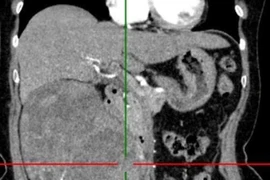

Lần này, khi trẻ được khám tại Liên chuyên khoa Tai Mũi Họng – Bệnh viện Nhi Hà Nội, kết quả nội soi tai phát hiện khối trắng ngà nằm phía sau màng nhĩ trái. Chụp cắt lớp vi tính tai xác định trẻ mắc cholesteatoma tai giữa bên trái – một bệnh lý có tính chất phá hủy xương, tiềm ẩn nguy cơ biến chứng nặng nề nếu điều trị muộn.

Hình ảnh tổn thương tai giữa gây nghe kém ở bệnh nhi. Ảnh BV